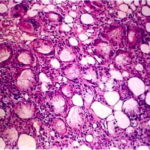

Histopathology. Focal areas of fat necrosis are present in the fat lobules and are infiltrated by macrophages and foreign body-type giant cells (Fig. 20-28). Fat deposits in the macrophages and giant cells contain crystalline fat, which after lipid extraction appears as needle-shaped clefts in a radial arrangement . In frozen sections, the radial clefts contain doubly refractile crystals. Calcium deposits usually are small and scattered in the necrotic fat. If the necrosis is |

differential Diagnosis . Both subcutaneous fat necrosis of the newborn and sclerema neonatorum have crystalline arrays of needle-like clefts in the fat. Sclerema is a catastrophic diffuse illness that gives little time for extensive inflammation; thus, in sclerema, there is an absence of focal areas of fat necrosis with macrophages and giant cells. In sclerema, there is also an absence of calcifications and the presence of wide bands of fibrous tissue in the subcutis . Treatment of children with high doses of steroids-for example, as was done for rheumatic fever-can produce poststeroid panniculitis with subcutaneous lesions very similar histologically to those of subcutaneous fat necrosis of the newborn . The deep nodules usually occur within 1 to 30 days after the cessation of high-dose steroid treatment. Traumatic fat necrosis has focal areas of necrosis and inflammation but lacks the crystals in the fat. Localized infection can be difficult to exclude clinically, but the infants with subcutaneous fat necrosis are generally rather healthy and are not septic. |